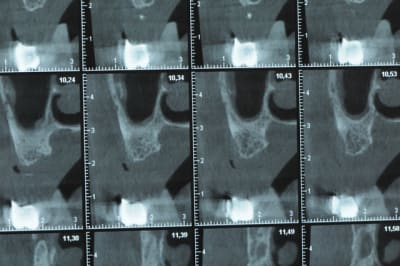

Une petite étude de ton cas D57

Sous réserves bien sur de voir l’animal en vrai

Les zones exploitables radiologiquement parlant:

Coupes implant

2,3 40100

4,96 35130 avec sinus lift mais difficile

5,25 35150

6,02 35130

6,78 35115 après réduction de hauteur de crête

7,26 35115 après réduction de hauteur de crête

8,51 35150

10,43 40115 ou 50115

11,10 40115

Ce qui nous fait 9 implants possible évidement avec un comblement de sinus on augmenterait encore les zones implantable mais ce n’est pas le but recherché, avec 8 (4+4) il doit être possible de faire une belle barre support de complet